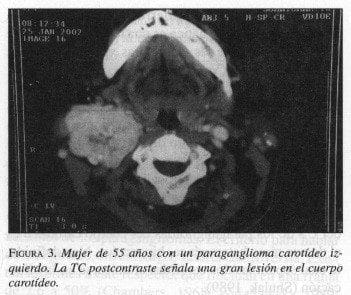

En la TC, después de la inyección de un bolo de contraste, los paragangliomas del cuerpo carotídeo aparecen como una masa hipervascularizada, localizada en la bifurcación de la carótida común (figura 3).

La separación de las carótidas interna y externa (signo de la lira) sugiere un paraganglioma del cuerpo carotídeo (Trimas, 1994). Aunque estas lesiones son típicamente hipervasculares, demostrando un intenso realce, se han informado lesiones avasculares.